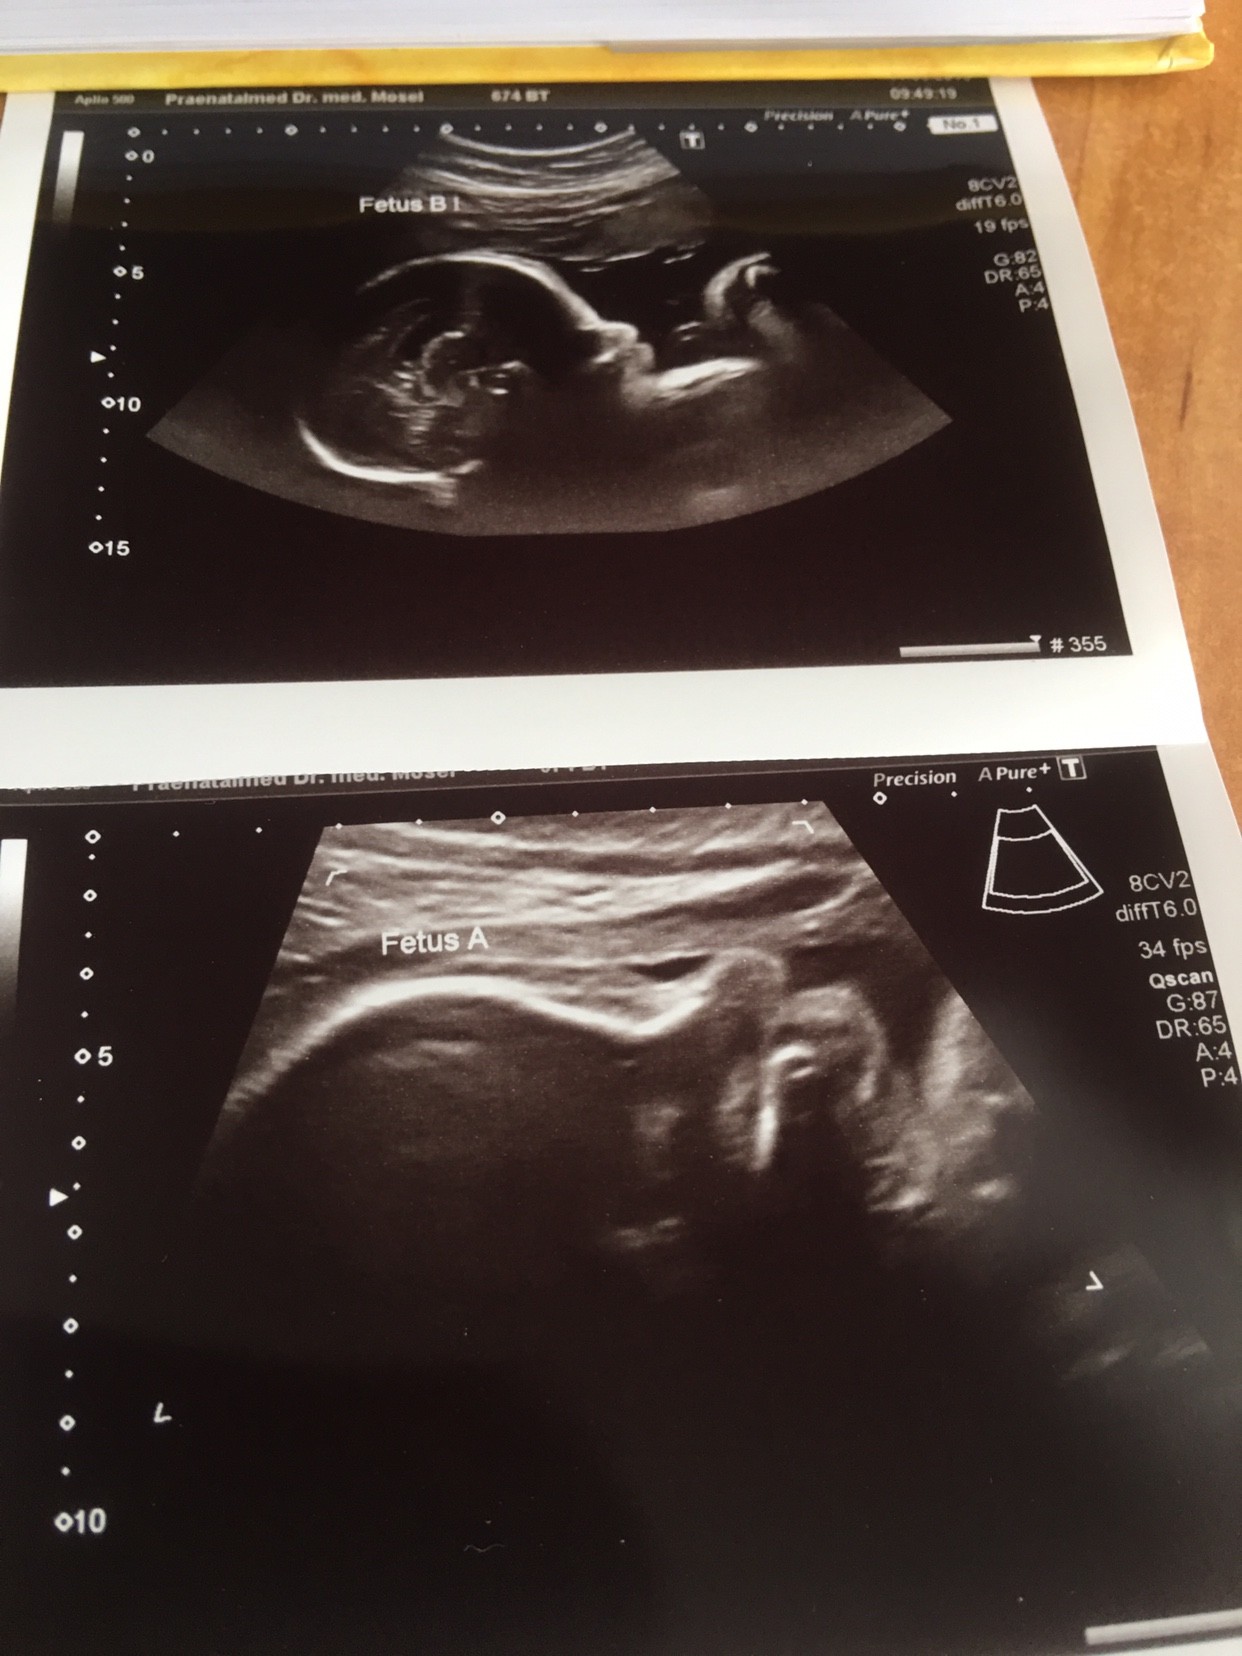

Czesc ciotki, my juz po fotoshooting , mamy 40 i 38 cm, wagowo 1550 i 1600 w 28plus 6 tc. Wszystko ok, szykujemy sie na sn, na cc nie ma na razie zadnych wskazan.

IMG_4444.JPG